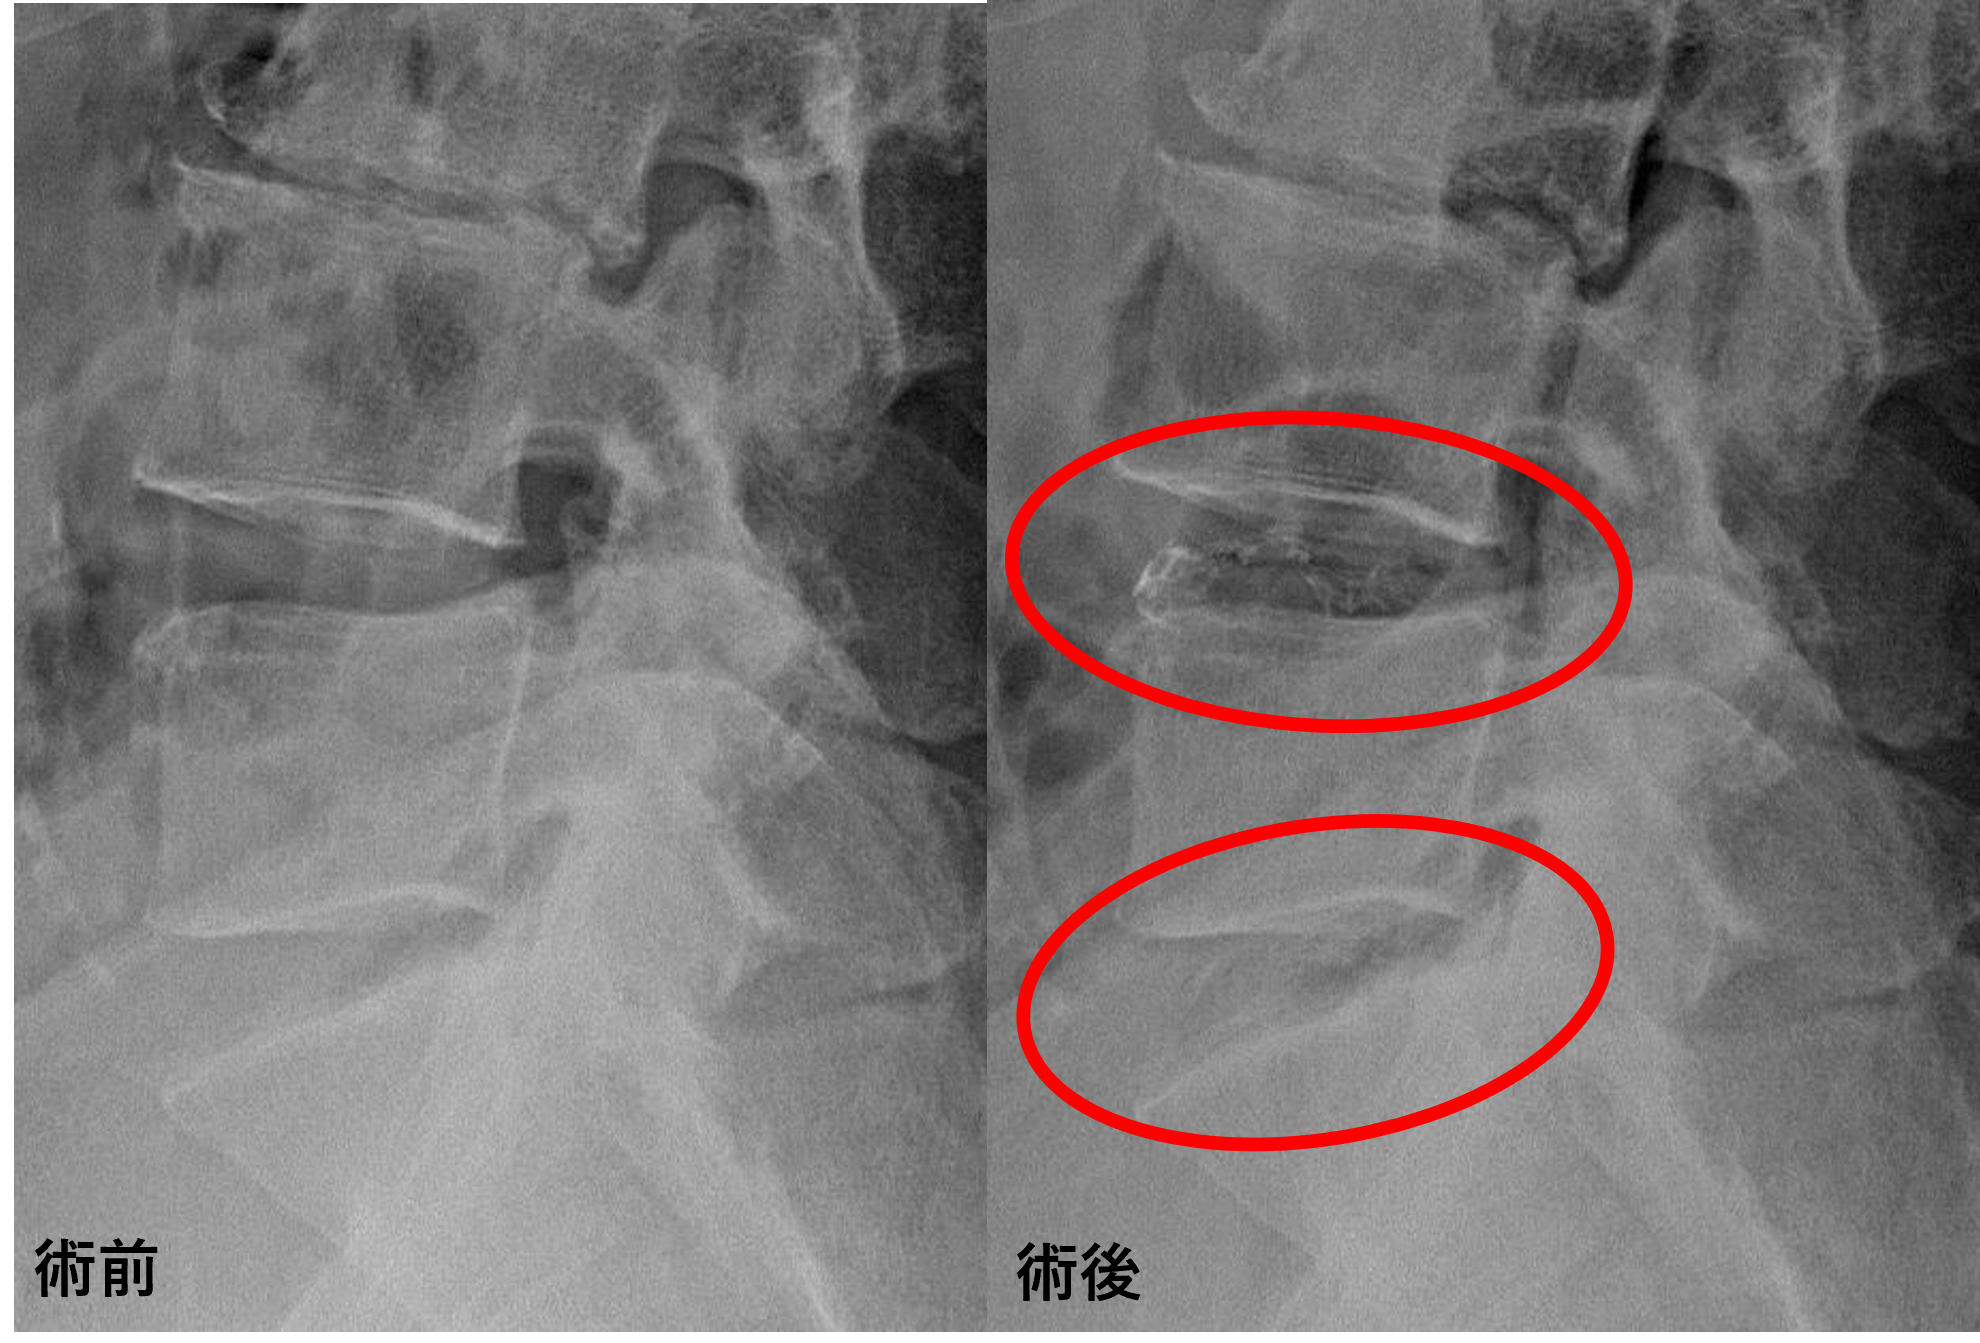

画像及び所見について

- L1/2 – 椎間板変性、膨隆

- L2/3、3/4 – 椎間板変性、椎間板減高、椎間孔狭窄

- L4/5 – 椎間板変性、膨隆、椎間孔狭窄、脊柱管狭窄、変性すべり

- L5/s – 椎間板変性、膨隆、椎間孔狭窄

以上のことが画像上認められました。

L4/5、5/sの椎間板所見による脊柱管の圧排が、症状の原因の可能性が高い。

患者様と相談の元、L4/5、5/sにセルゲル法を施行